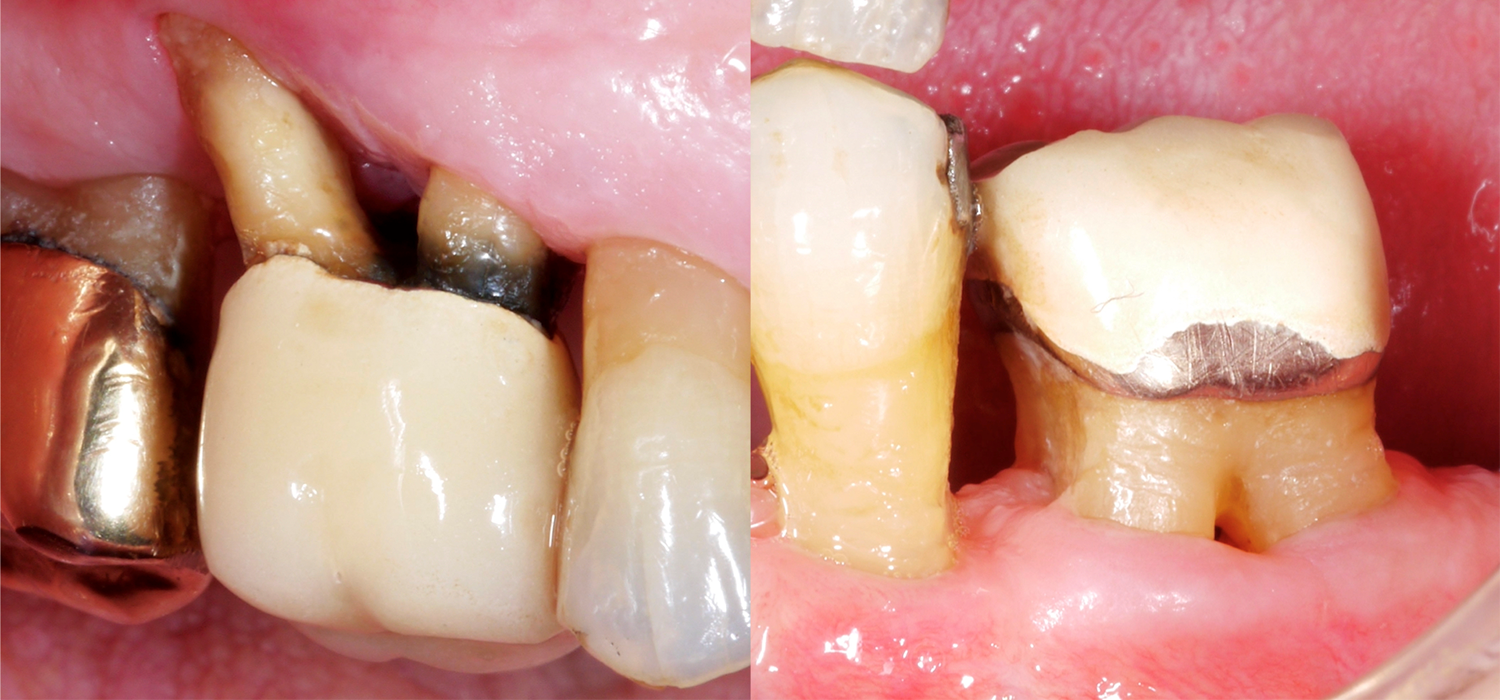

When it comes to teeth, those with multiple roots are, of course, often much more difficult to treat, especially if they present furcation defects. Why is the furcation area so challenging? In comparison to single-rooted teeth, access for mechanical cleaning of the root surface is much more difficult, the furcation entrance can often be very small/narrow, and there may also be further anatomical particularities, such as enamel projections.